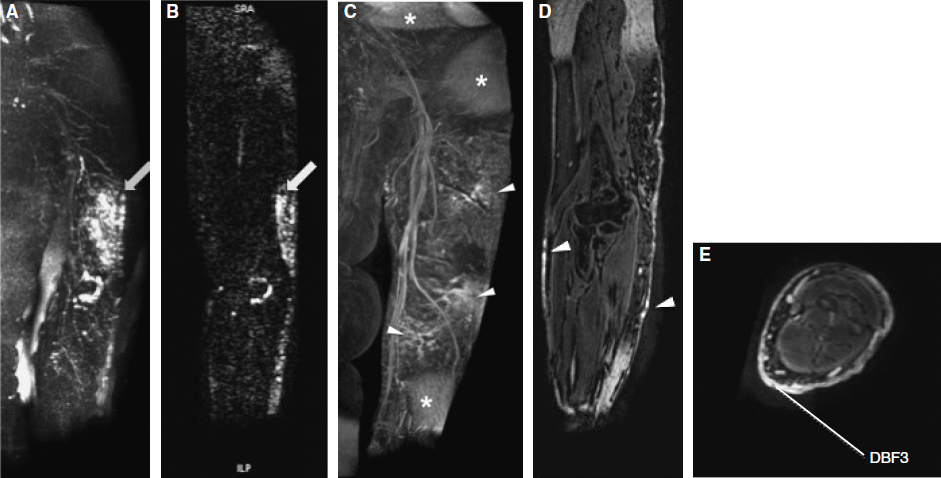

Two primary sequences are included in our MRL examination: (1) a heavily T2-weighted three-dimensional turbo spin-echo with spectral fat suppression (spectral presaturation with inversion recovery) to define the severity and extent of edema and (2) a dynamic T1-weighted three-dimensional spoiled gradient–recalled echo (3D T1w GRE) with fat suppression before and after the intracutaneous contrast injection to visualize enhancing lymphatic channels and dermal backflow (Figs. 28-1 and 28-2). Example MR sequence parameters used at our institution are presented in Table 28-1.

Currently we perform seven dynamic phase acquisitions at approximately 5-minute intervals (0, 5, 10, 15, 20, 25, and 30 minutes). 17 After these initial dynamic phases are acquired, the images are reviewed to determine if additional phases are needed to include the entire extent of lymphatic enhancement. After the MRL, we perform an MR venogram to help differentiate subdermal lymphatics from veins. For the MR venogram, a single phase of the 3D T1w GRE scan used for the MRL is repeated 120 to 180 seconds after an intravenous injection of MR contrast. The three-dimensional scans of the upper or unilateral lower extremities are performed in the sagittal orientation for more efficient scanning. The three-dimensional scans of the bilateral lower extremities are performed in the coronal orientation for the larger lateral scan coverage needed to include both lower extremities in the same scan field of view. Currently at our institution, the average examination time for an upper or lower extremity MRL is between 1.5 and 2 hours.